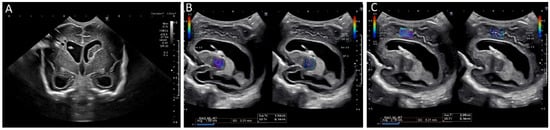

Brain tissue stiffness is also affected by hydrocephalus (Figure 8). In a prospective study using SWE, the brain stiffness of healthy neonates was compared to that of neonates with hydrocephalus [65]. Hydrocephalus was associated with greater tissue stiffness, and SWE measurements were positively correlated with intracranial pressure [65]. Transtemporal SWE in adults shows a similar correlation between stiffness and intracranial pressure [54], and this may be a viable approach in children with closed fontanelles.

Figure 8.

Ultrasound elastography of a 2 month old, former 28 week and 4 day infant with posthemorrhagic hydrocephalus after shunt placement. (A) A grayscale image demonstrating a right shunt catheter terminating in the right frontal horn. Periventricular cystic changes are seen related to prior infarct. Elastography measurements were taken over (B) the right basal ganglia, with values of 1.55 m/s and (C) the periventricular white matter with values of 2.18 m/s (C). These images were initially published in Pediatric Neurology, Volume 86, by authors Danielle deCampo MD PhD and Misun Hwang MD in the article “Characterizing the neonatal brain with ultrasound elastography,” pages 19–26, Copyright Elsevier (2018).